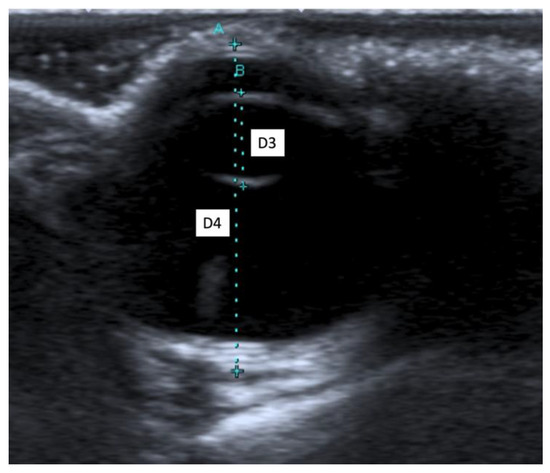

2.4. Ultrasound Biometric Measurements

3.2. Ultrasound Biometric Measurements

| (a) | |||||||||||||||

| Both breeds | OS 1 (n 3 = 27) | OD 2 (n 3 = 27) | Mean OS 1 + Mean OD 2 | ||||||||||||

| D1 5 | D2 6 | D3 7 | D4 8 | D5 9 | D1 5 | D2 6 | D3 7 | D4 8 | D5 9 | D1 5 | D2 6 | D3 7 | D4 8 | D5 9 | |

| Mean (mm) | 1.68 | 7.41 | 4.29 | 15.09 | 18.01 | 1.66 | 7.48 | 4.32 | 15.16 | 18.07 | 1.67 | 7.44 | 4.30 | 15.12 | 18.04 |

| SD 4 (mm) | 0.16 | 0.18 | 0.11 | 0.44 | 0.49 | 0.16 | 0.20 | 0.17 | 0.37 | 0.49 | 0.12 | 0.17 | 0.12 | 0.37 | 0.43 |

| Median (mm) | 1.70 | 7.40 | 4.30 | 15.20 | 18.10 | 1.70 | 7.50 | 4.30 | 15.20 | 18.00 | 1.65 | 7.45 | 4.30 | 15.05 | 18.05 |

| Maximum (mm) | 2.10 | 7.70 | 4.50 | 15.80 | 18.80 | 1.90 | 7.80 | 4.70 | 15.90 | 18.90 | 1.95 | 7.75 | 4.55 | 15.80 | 18.85 |

| Minimum (mm) | 1.40 | 7.00 | 4.10 | 14.30 | 16.80 | 1.30 | 7.10 | 4.10 | 14.60 | 17.30 | 1.45 | 7.05 | 4.10 | 14.50 | 17.25 |